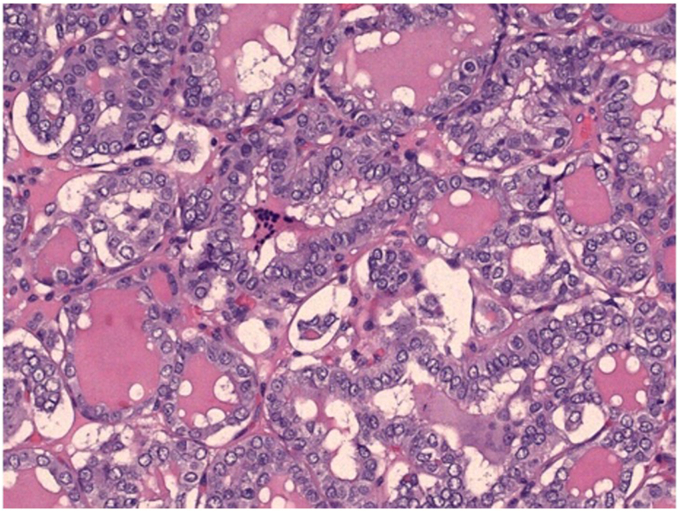

Our case describes a 24-year-old woman who initially presented with a right lateral neck lump. This was thought to be a lipoma, and no workup was performed until it began to grow during pregnancy 3 to 4 years after initial presentation. The patient underwent excision with findings of a level 5B lymph node with pathology consistent with PTC, follicular variant. Neck ultrasound performed in an imaging center and in our clinic did not reveal thyroid nodules or abnormal appearing lymph nodes. Solid tumor profiling assay identified a neurotrophic tropomyosin receptor kinase (NTRK)-3 fusion: ETV6(4)-NTRK3(14) mutation.